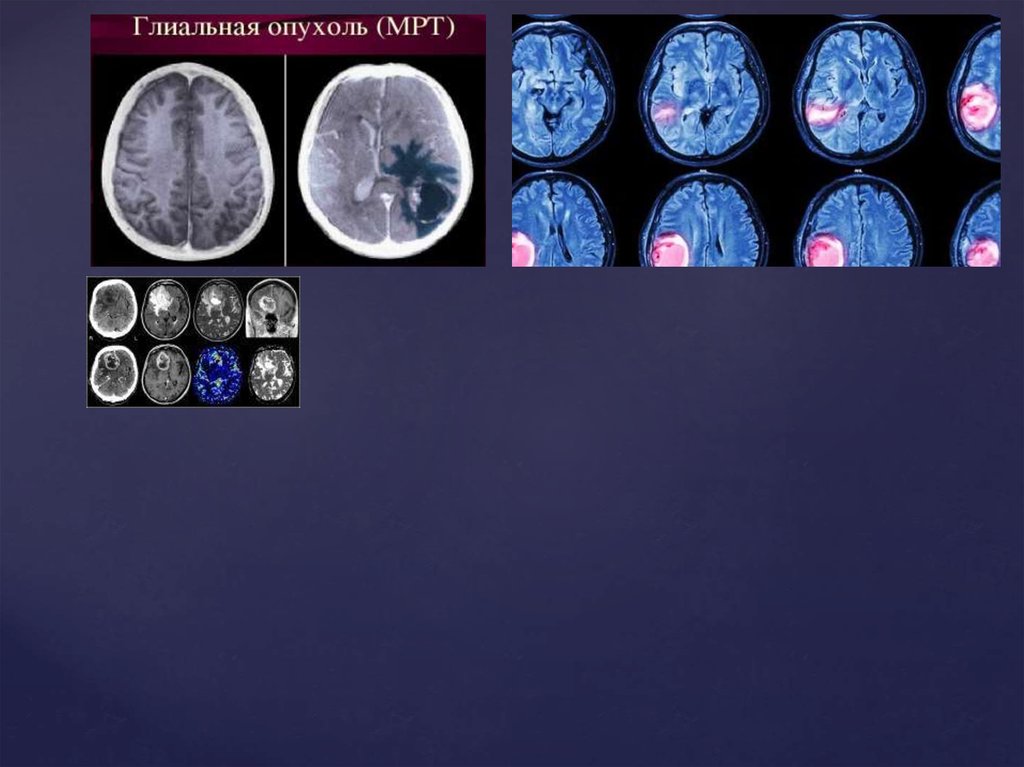

Опухоли головного мозга